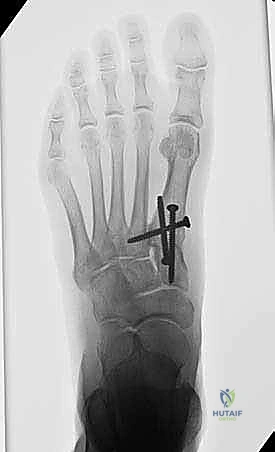

بعد التأكد من المحاذاة المثالية، يتم تثبيت العظام بشكل دائم. يستخدم الأستاذ الدكتور محمد هطيف أحدث التقنيات العالمية في التثبيت، والتي تشمل عادة مسامير تيتانيوم متقاطعة (Crossed Screws) أو شريحة معدنية متخصصة مع مسامير (Plating System) لضمان أقصى درجات الثبات والضغط بين العظمتين، مما يسرع من عملية الالتئام.

- المتابعة الإشعاعية: يتم إجراء أشعة سينية للتأكد من بدء التحام العظام.

- تحمل الوزن: إذا كانت الأشعة مطمئنة، يُسمح بالانتقال التدريجي لتحميل الوزن الكامل أثناء ارتداء الحذاء الطبي، ثم الانتقال لاحقاً إلى حذاء رياضي واسع ومريح.